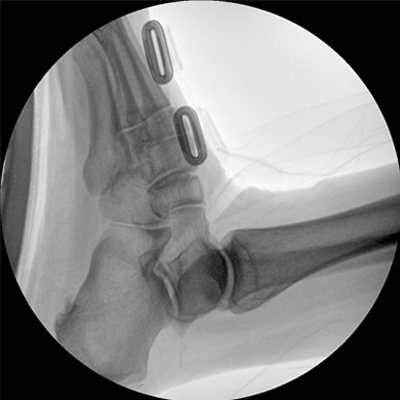

四維電動(dòng)運(yùn)動(dòng)控制,平滑定位,使得復(fù)雜角度快速實(shí)現(xiàn)。

專業(yè)的圖像處理系統(tǒng),為您提供高分辨率、高灰階圖像。